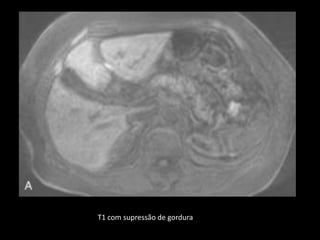

ANATOMIA RM NORMAL

Depende da sequência de pulsos escolhida;

T1: sinal mais forte que tecidos não adiposos,

como o fígado e os músculos, devido ao conteúdo

proteico aquoso.

T1 com supressão de gordura: ↑sinal;

T2: ligeiramente hiperintenso em relação ao

músculo;

T2 com supressão de gordura: contraste com a

gordura adjacente é mínimo.

T1 com supressão de gordura